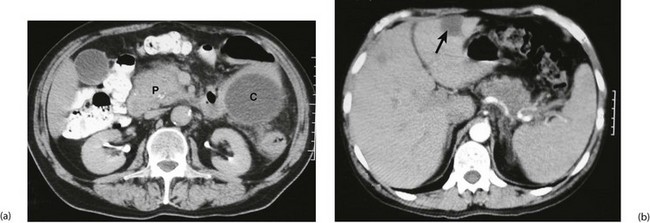

When pancreatic cancer is suspected in a non-jaundiced patient, abdominal CT can confirm the diagnosis more reliably than ultrasound, although small tumours may be missed (see Fig. 24.2a and b). CT scanning also indicates retroperitoneal and portal vein invasion; it shows metastases in liver and lymph nodes and CT-guided needle biopsy can obtain histopathology specimens, all of which can determine resectability. CT scanning can understage the disease, chiefly because it does not detect small-volume hepatic and peritoneal deposits.